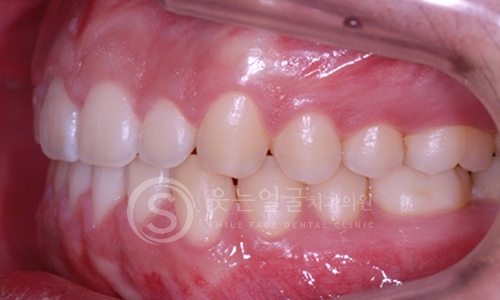

한눈에 보는

치아교정 전후사진